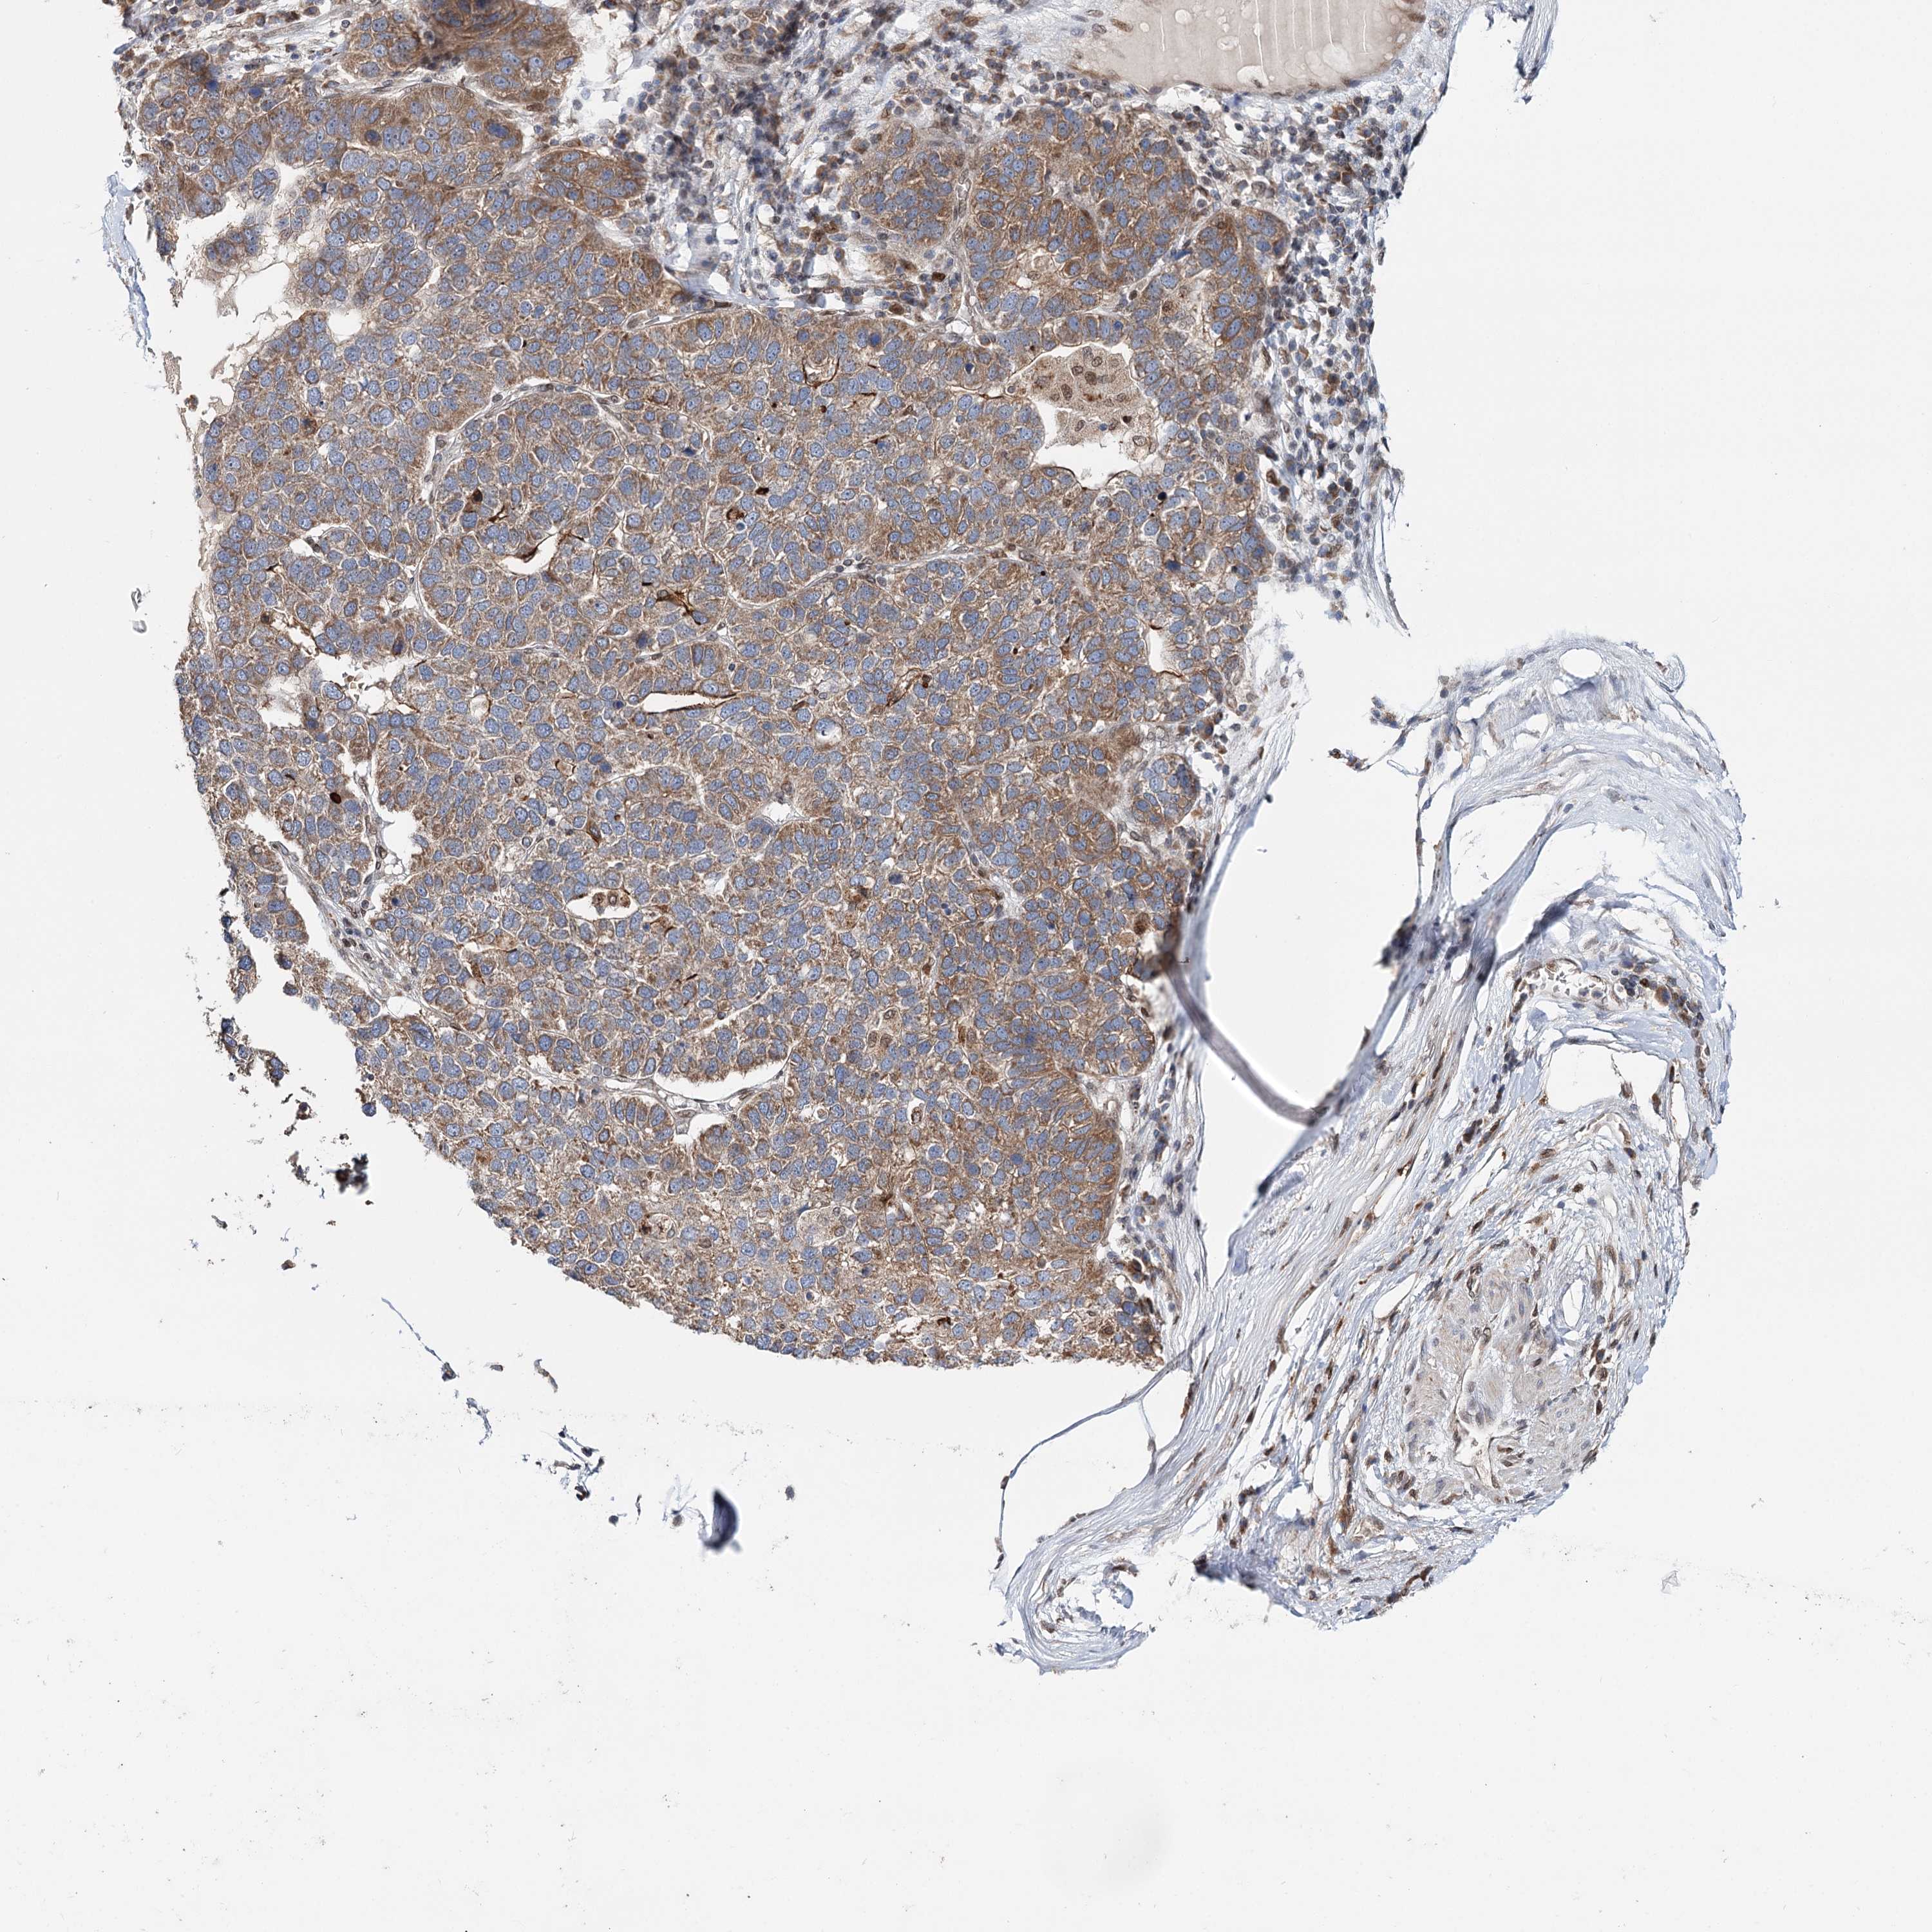

PANCREATIC CANCER - Protein expressioni

A mouse-over function shows sample information and annotation data. Click on an image to view it in a full screen mode. Samples can be filtered based on level of antibody staining by selecting one or several of the following categories: high, medium, low and not detected. The assay and annotation is described here.

Note that samples used for immunohistochemistry by the Human Protein Atlas do not correspond to samples in the TCGA dataset.

Antibody stainingi

Antibody staining in the annotated cell types in the current human tissue is reported as not detected, low, medium, or high, based on conventional immunohistochemistry profiling in selected tissues. This score is based on the combination of the staining intensity and fraction of stained cells.

Each image is clickable and will lead to virtual microscopy that enables deeper exploration of all samples and also displays staining intensity scores, fraction scores and subcellular localization as well as patient and tissue information for each sample.

Antibody HPA037786

Antibody HPA038034

Antibody HPA038867

Antibody HPA038868

Staining

High

Medium

Low

Not detected

Intensity

Strong

Moderate

Weak

Negative

Quantity

>75%

75%-25%

<25%

None

Location

Nuclear

Cytoplasmic/membranous

Cytoplasmic/membranous,nuclear

Adenocarcinoma, NOS